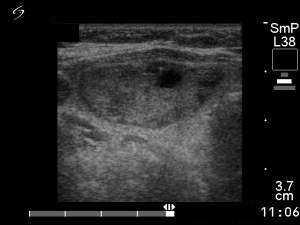

Four months before the sclerotherapy (first row of images):

Clinical presentation: a 45-year-old woman with an autonomously functioning adenoma known for 3 years was referred for evaluation. Her TSH level decreased continuously but was normal until the last checking. She had no complaints.

Palpation: a moderately firm nodule in the right lobe.

Hormonal investigation indicated euthyroidism (FT4 15.9 pM/L) with a subnormal TSH (0.19 mIU/L).

Ultrasonography: the thyroid was echonormal. There was a moderately hypoechogenic nodule in the left lobe. The lesion displayed halo sign.

Suggestion: TSH-test every six months.